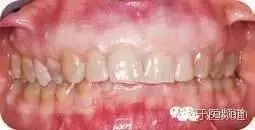

口內(nèi)檢查

● 患者已掌握正確的刷牙和使用牙線的技巧。

● 軟組織:唇,頰黏膜,軟硬腭,口底和舌的色、形、質(zhì)及紋理正常。

● 臨床檢查中未發(fā)現(xiàn)齲壞。部分修復(fù)體邊緣脫落。

● 下后牙舌側(cè)牙齦輕度發(fā)紅,并伴有輕度探診出血(圖1,圖2)。

● #8、9之間系帶附著較高。下頜前牙區(qū)牙槽嵴輕度骨性肥大。下前牙磨耗擁擠,#23向唇側(cè)-遠(yuǎn)中方向旋轉(zhuǎn)。